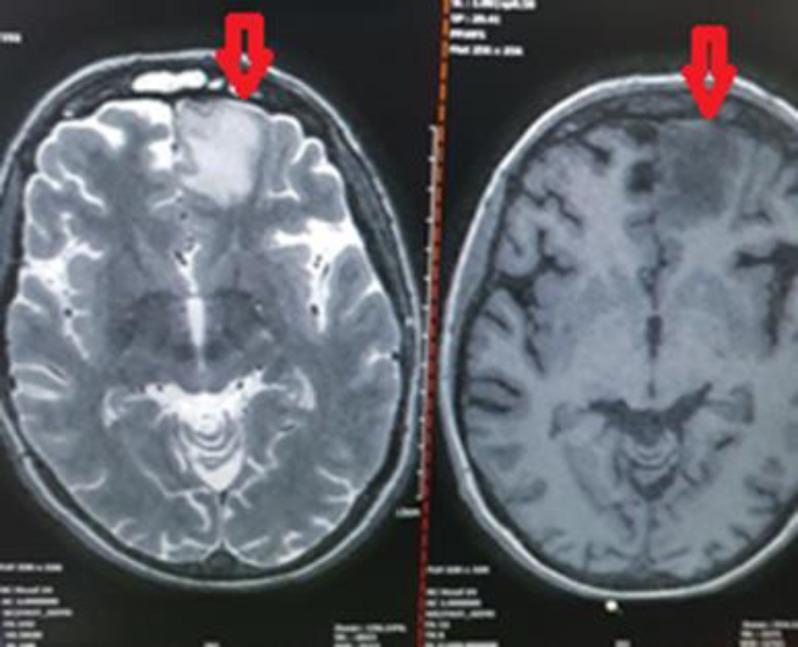

Herein, we present the case of a 35-year-old woman with diagnosis of B-cell lymphoma and rhino-orbito-cerebral mucormycosis (ROCM). She was a candidate for enucleation of the left eye, orbital decompression, and sinocerebral debridement. Nevertheless, the patient refused eye enucleation and craniotomy. Finally, she was treated with a combination of antifungals and sinus debridement without eye enucleation and craniotomy.

在此,我们报告一例35岁诊断为B细胞淋巴瘤合并鼻眶脑毛霉病(ROCM)的女性病例。她曾是左眼摘除、眼眶减压和鼻窦脑清创术的候选者。然而,患者拒绝眼球摘除和开颅手术。最后,她接受了抗真菌药物联合鼻窦清创治疗,未进行眼球摘除和开颅手术。